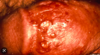

What is this image Herpes Simplex 1 Herpes Simplex 2 HPV 6 HPV 16 HPV 18

**Herpes Simplex 1** Herpes Simplex 2 HPV 6 HPV 16 HPV 18